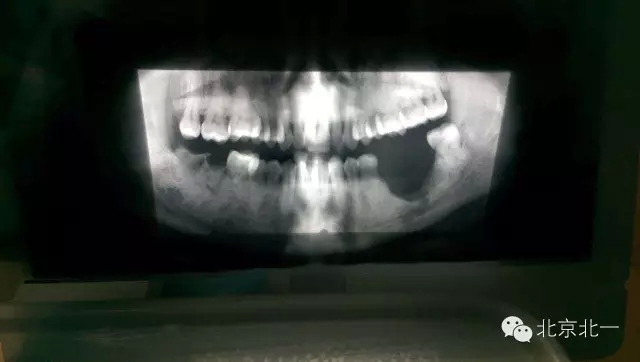

先看一例病例吧?拔牙前全景片。

圖二:拔牙后骨壞死,后被診斷為石骨癥,作為牙醫(yī)如果你還戰(zhàn)斗在拔牙一線,請正確認(rèn)識石骨癥。(這是《北一微創(chuàng)拔牙班內(nèi)部教材》局部章節(jié)節(jié)選病例分析)